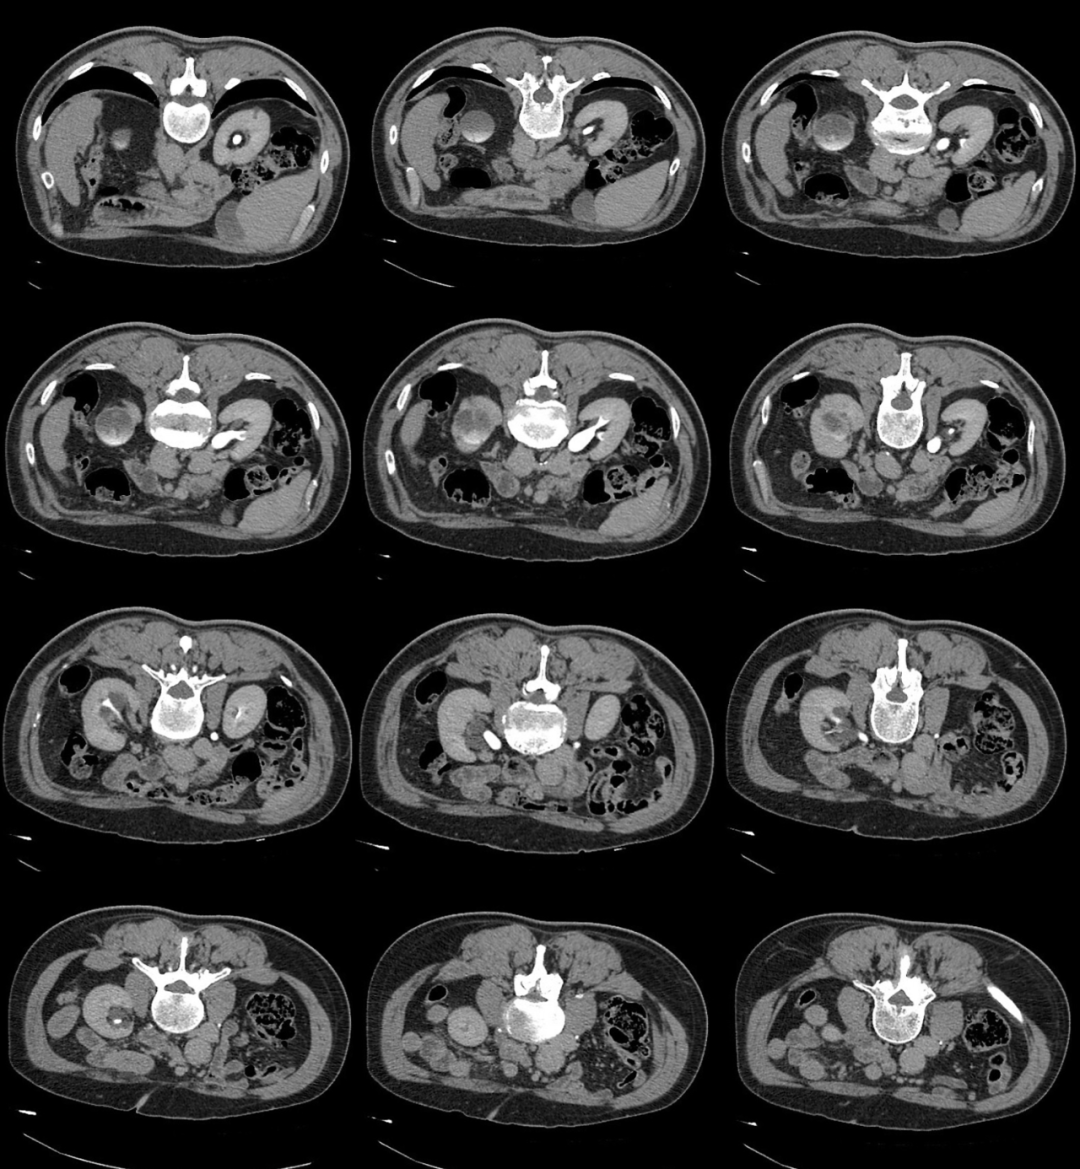

笔者:你跟患者说,让他再起来到门口不要走开,等 15 分钟后再给回来扫一次,仰卧位扫一次,俯卧位扫一次;

技师:为什么啊,干啥还是俯卧位扫描?

笔者:等 15 分钟后我再告诉你,:

15 分钟后,患者再次扫描

俯卧位

笔者:你看看发现什么不一样的嘛?

技师:咦!这个囊肿和以前的囊肿不一样啊,它怎么会发生强化呢?

笔者:这真的就是囊肿嘛?

2、肾盏憩室主要表现为:肾内囊性占位,平扫时囊性灶与肾盏分界不清,增强后造影剂进入囊肿(主要在延迟期造影剂进入憩室内);有时囊肿内可以看到结石或者钙乳样沉积物;肾盏憩室病灶主要偏向外周生长。